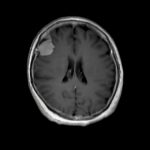

断層撮影

手術前1